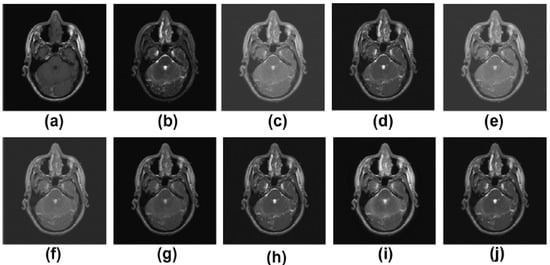

5.2. Results and Discussion